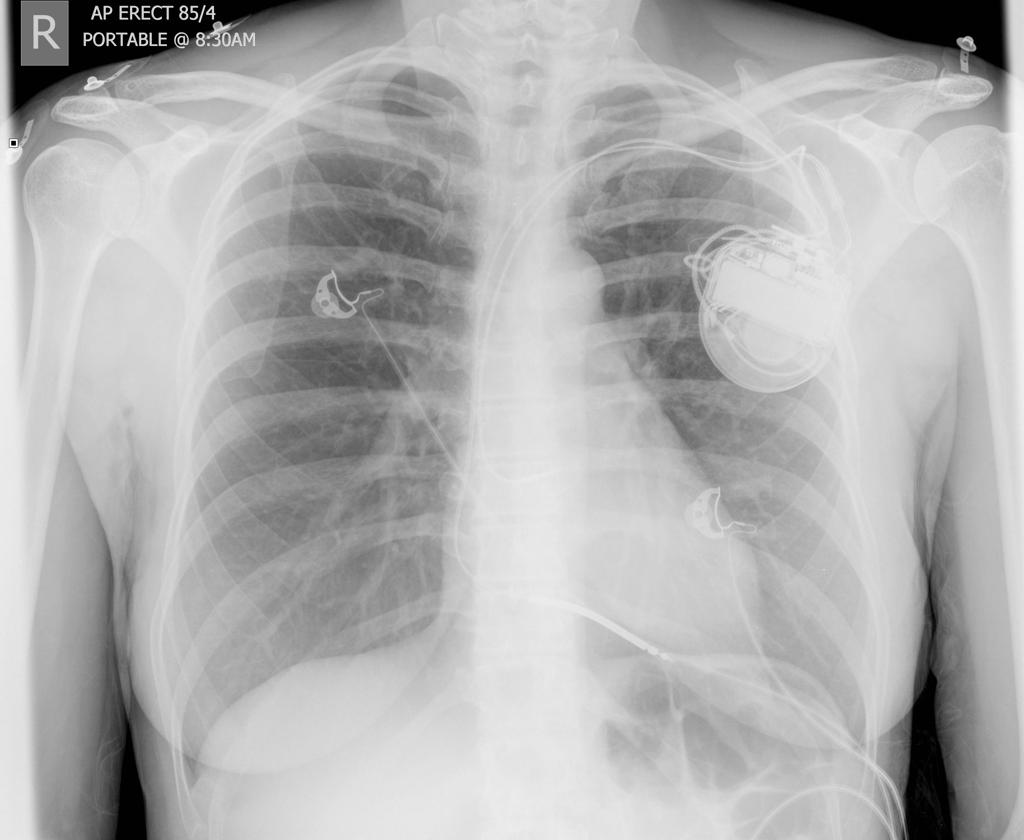

Pacemaker

pacemaker.jpg